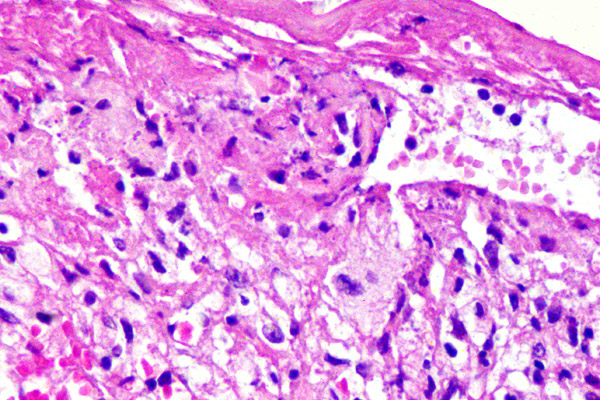

En las fases agudas, la lesión es rica en parásitos y en el infiltrado predominan los macrófagos espumosos cargados de parásitos y una respuesta celular mixta de tipo histiocitaria.

El diagnóstico definitivo requiere la identificación de la forma intracelular del parásito: el amastigote de Leishmania (o corpúsculo de Leishman-Donovan), observados con coloración de PAS, en esta imagen, en las áreas señaladas con elipses.

A mayor aumento se aprecian los macrófagos espumosos cargados de parásitos, teñidos de magenta con coloración de PAS, Estos amastigotes son cuerpos redondos u ovalados, pequeños, de 2 – 5 µm de diámetro, de ubicación intracelular exclusiva.

Con la tinción de Giemsa se tiñen los amastigotes. El estudio histológico de estas lesiones es necesario para descartar malignidad u otras causas granulomatosas (tuberculosis, micobacterias atípicas, sarcoidosis, etc.). Las coloraciones son necesarias para identificar microorganismos.